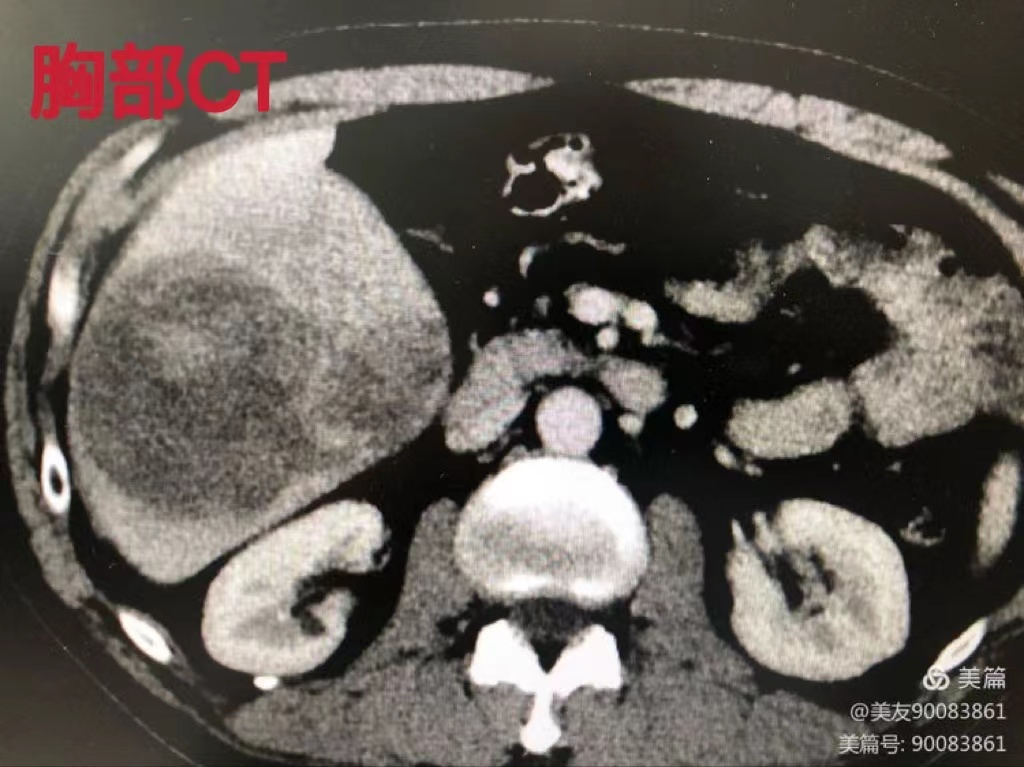

患者男性,51岁,因右上腹疼痛20余天来我院就诊,检查后诊断为肝右叶巨大肝癌收治入院,入院后完善相关辅助检查,经全科讨论,决定行腹腔镜下解剖性肝右后叶切除术,因腹腔镜下S6、S7段切除位置特殊,显露困难,一直被业界认作是腹腔镜肝脏手术的巅峰。我院肝胆胰外科主任祁向军带队科室,经过术前准确评估肝功能,残肝体积及肿瘤与血管之间的关系,由祁向军主任主刀,郭雅明、满泉副主任医师协助。术中精确结扎肝右动脉右后支,分离显露门静脉右支,解剖出肝右后叶Glisson鞘,并分出门静脉右后上支及右后下支给予结扎,给予间断阻断肝门,完整切除肿瘤及肝右后叶,手术顺利,患者术后恢复较好,肝功能恢复正常!